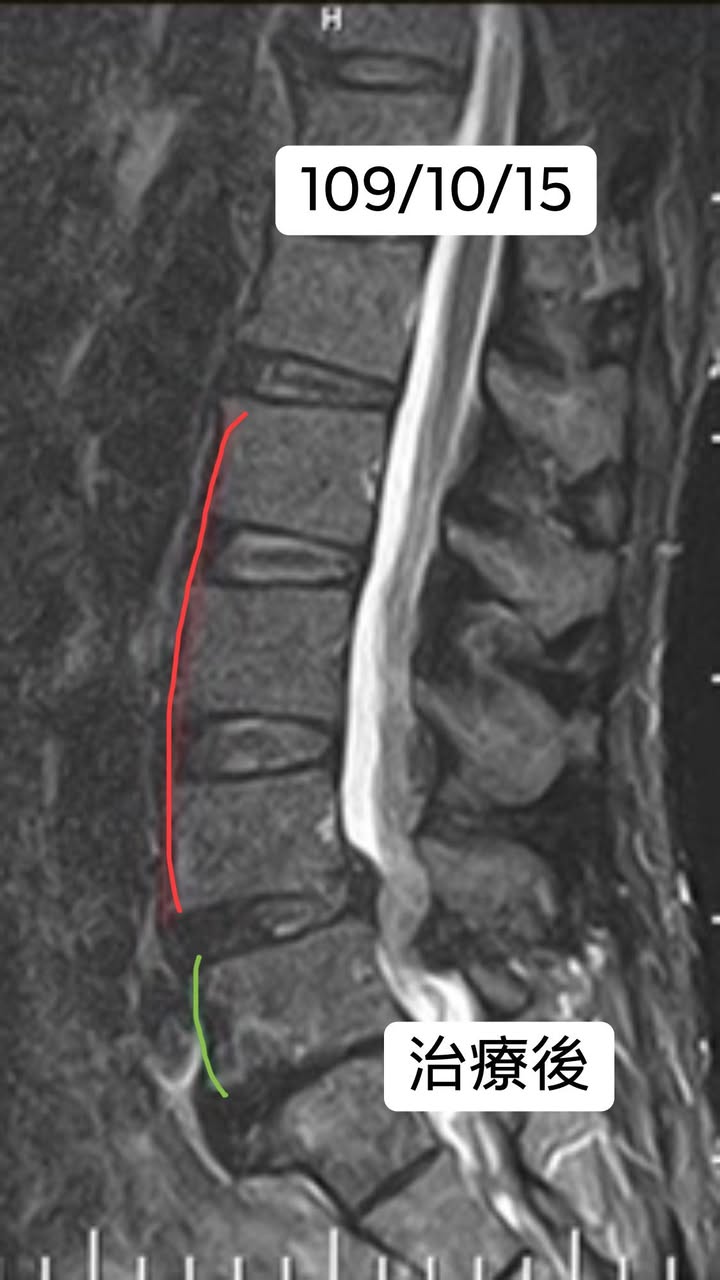

第一圖是grade I 滑脫

第二張圖雖然還是grade I滑脫,但骨頭連續性出現了,不像一開始有比較明顯位移,症狀完全消失,疼痛完全不見,走路比之前輕鬆太多。